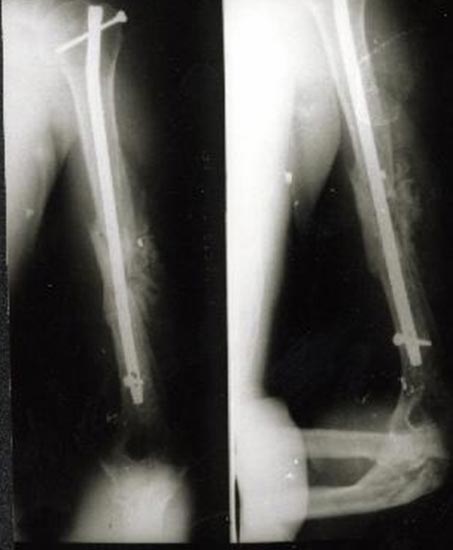

病例四、

肱骨骨不连的骨断端多有硬化而骨干骨质疏松、遗留有以往手术的钢板、

钉孔,骨吸收骨干变细有严重骨缺损,治疗困难较大。

带锁髓内钉内固定,解决骨质疏松、骨干变细和骨缺损等情况

下的固定问题,进行复合骨髓细胞的植骨,促进骨折愈合